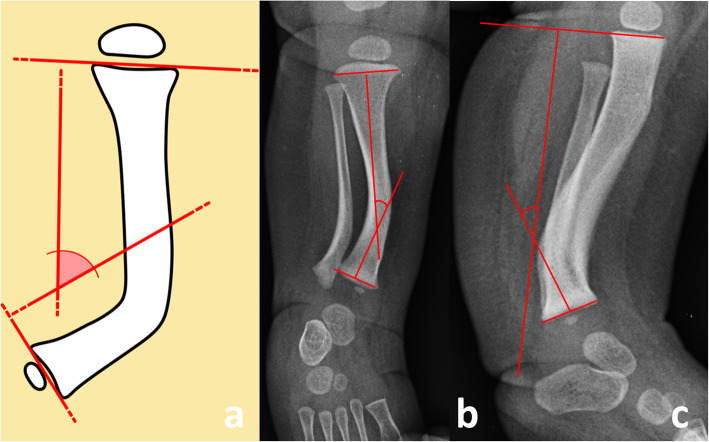

The following variables were measured on serial sequential radiographs in order to assess the initial deformity and the spontaneous remodeling:1) the anteroposterior interphyseal angle (AP-IPA) and the lateral interphyseal angle (L-IPA), that are the angles measured between a line perpendicular to the proximal physis and a line perpendicular to the distal physis, on true anteroposterior and lateral views of the leg, respectively [2] Positive AP-IPA indicates medial bowing, while negative AP-IPA indicates lateral bowing. Positive L-IPA indicates posterior bowing, while negative L-IPA indicates anterior bowing (Fig. 1);

Fig. 1.

Schematic drawing of the tibia (1a), anteroposterior (1b) and lateral (1c) radiographs of the leg in a 1-month old baby. The interphyseal angle (IPA) is measured between a line perpendicular to the proximal physis and a line perpendicular to the distal physis on a true anteroposterior (AP-IPA) and a true lateral (L-IPA) view of the leg, respectively